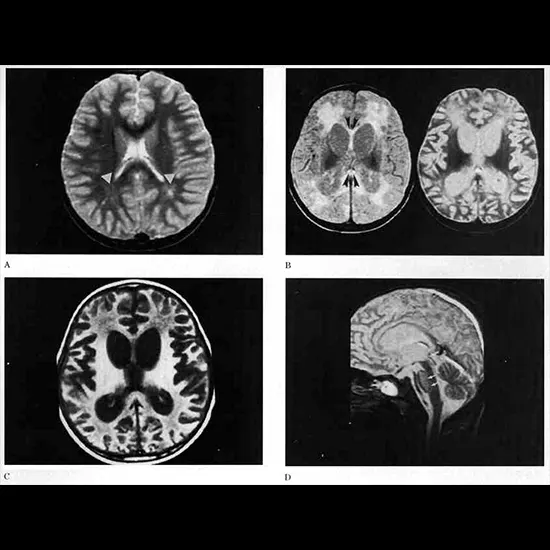

Subacute sclerosing panencephalitis (SSPE), moreover known as Dawson illness, may be an uncommon frame of dynamic brain irritation caused by a diligent disease with the measles infection. The condition essentially influences children, teenagers, and youthful grown-ups.

MRI Brain with contrast 11500 5750